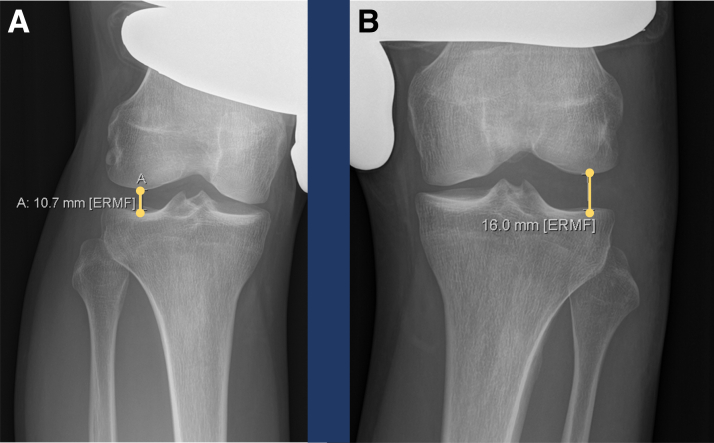

Multiple ligament knee injuries may occur with knee dislocations in high-energy traumatic causes, low-energy mechanisms like athletic injuries, or in ultra-low velocity injuries, seen in the severely obese.1, 2, 3 These are complicated conditions to assess and treat, because diverse combinations of injury may be seen to the ligaments, tendons, and neurovascular structures of the knee. Advanced trauma and life support and assessment of vascular status may be necessary because of the frequency of vascular injuries in knee dislocation and the traumatic etiology of many of these injuries.1,2 A thorough physical examination and multimodal imaging evaluation is required. Lachman, posterior-drawer, varus, valgus and rotational testing are useful to determine the nature and scope of injuries, and supplementation with posterior, varus, and valgus stress radiographs provides an accurate picture of the integrity of major stabilizing ligaments (Figs 1 and 2).4, 5, 6 A foot-drop indicates common peroneal nerve involvement. Magnetic resonance imaging is additionally used to detect concomitant meniscal, nervous, muscular, or other injuries and bony edema and cartilage damage (Fig 3).2

Fig 2.

Varus stress radiographs are a validated method to assess for fibular collateral ligament (FCL) and posterolateral corner (PLC) injuries. Proper technique in taking the radiograph is essential. Increased side-to-side difference with clinician-applied varus gapping of 2.2 to 2.7 mm should raise suspicion of a complete FCL tear or grade III posterolateral corner injury if gapping is increased more than 4.0 mm on the injured side compared to the uninjured side. In the above images, 16.0 mm gapping is measured with varus stress on the injured left knee (A), whereas 10.7 mm is measured on the uninjured right side (B). This difference of 5.3 mm may indicate complete (grade III) posterolateral corner injury.